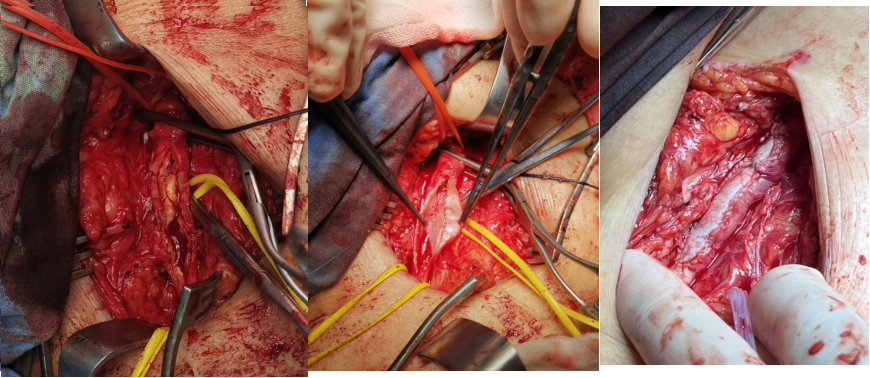

图为:左股动脉内膜剥脱

图为:术前造影:腘动脉P3胫前起始部显影

图为:导丝进入ATA,远端无法回真腔

图为:足背动脉穿刺对接